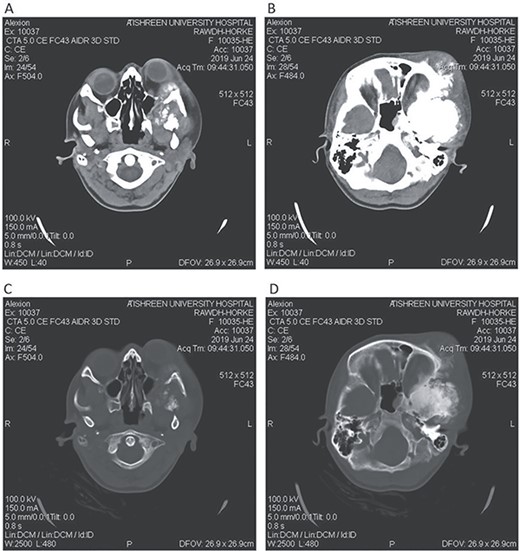

CT head tissue window (A, B). A. Invasion of the maxillary sinus and orbit. B. Invasion of the parietal, temporal and frontal lobes. A remarkable exophthalmos. Bone window (C, D). C. The bone-forming lesion showing the same density of the bone. D. Invasion of the sphenoid, temporal and parietal bones.

A 17-year-old female presented with a history of osteosarcoma that was confirmed after undergoing a surgery to remove an enlarging bone tumor in the left temporal region 2 years ago. She later got pregnant and delivered her child but never got back for a checkup until she was admitted to our hospital with a severe and unresponsive to medication headache that progressed over the course of 6 months and blurred vision that progressed to complete left-sided vision loss. Physical examination revealed a tough and mobile yet fixed at the base 7-cm mass towards the left of the frontal bone. Many more masses were revealed in the left side of the skull including the anterior cranial fossa, orbit, base of the skull and the left part of the occipital region where the previous procedure was performed (Fig. 1). These masses had been increasing in size probably under the influence of pregnancy hormones causing pain that radiated along the orbital and maxillary branches of the left trigeminal nerve. Physical examination and past medical history were otherwise unremarkable. Laboratory tests were all normal, and her family history was negative. Staging studies showed no evidence of distant metastatic disease in the chest, the abdomen and the pelvis. CT scan of the skull revealed a bone-forming non-lytic lesion accompanied by periosteal reaction. This lesion bulges to the outside towards the scalp spreading into both the soft tissues and the inside of the entire left side of the skull with a sunburst-pattern (Figs 2 and 3). Its rims are unsymmetrical and pointy, and it bulges into the left orbit outside the muscles causing exophthalmos with a semi-complete proptosis of the eyeball out of the orbit (Figs 2 and 3). This lesion applies pressure to the left frontal and temporal lobes causing mild edema in both these lobes without invading the brain tissue. This edema in turn applies pressure to the left lateral ventricles (minor shift of the elements of the midline to the right side can be seen on CT) (Fig. 4). Due to the tumor’s wide spread, the surgical procedure was performed in two stages (approximately 6-hour-long each). In the first stage, the bone mass was removed through a procedure of wide skull approach including the frontal, temporal and parietal bones and a removal of the invading part of the temporal muscle. Moreover, the lateral wall and roof of the left orbit were removed, the left optic nerve was dissected free and part of the meninges was removed and replaced with an autogenic patch from the fascia lata. Then, the bone loss was compensated for by using bone cement Synicem VTP (poly methyl methacrylate and Barium sulfate), and the orbit was rebuilt; the eyeball was placed back with noticeable decline of the exophthalmos. In the second stage, a complementary left parietal occipital incision of the previous approach was performed 3 weeks later; the remaining of the frontal and occipital bones was removed, and a partial mastoid surgery was done. Furthermore, the cavernous sinus were revealed and found to be not invaded. Later on, the normal skull shape was restored using the same cement. The histopathology of the lesion revealed proliferation of neoplastic chondroblasts, osteoblasts and spindle-shaped cells. The features are consistent with low-grade chondroblastic osteosarcoma (Fig. 5). The patient did not need ICU admission. She recovered well 3 days after the surgery and was discharged with no deficits. A CT scan that was performed post-operatively revealed that the masses were successfully excised (Figs 6 and 7). At the last follow-up 1 month post-operation, the patient was scheduled to undergo a course of radiotherapy, 60 Gy of radiotherapy in 30 fractions over 4 weeks without chemotherapy, as it is not recommended with low-grade osteosarcoma.